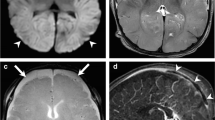

One child had isolated non-terminal long-segment venous thrombosis without any vascular disruption (Fig. 7). This case, a 3-month-old boy, presented with unusual cry, stiffening of his extremities and pallor. No history of trauma was provided but he had facial bruising and a right parietal fracture, both indicating impact trauma, and retinal hemorrhages. Neuroimaging demonstrated bilateral supratentorial and posterior fossa subdural hemorrhage, with thrombosis of the left vein of Labbé. We interpreted the venous thrombosis to be post-traumatic because (1) there was other evidence of cranial trauma and (2) bilateral supratentorial and infratentorial subdural hemorrhage is incompatible with a unilateral venous thrombosis.

Thrombosis in a 3-month-old boy who presented with unusual cry, stiffening of extremities and pallor. No history of trauma was provided, but facial bruising, right parietal skull fracture and retinal hemorrhage were present. a Coronal head CT demonstrates bilateral supratentorial and posterior fossa subdural collection (white arrows) with hyperattenuation in the region of the left vein of Labbé (black arrow). b Axial T2 and (c) axial T2* gradient recalled echo MR sequences show thrombosis of the vein of Labbé (arrow). d MR venography demonstrates absence of vein of Labbé, consistent with thrombosis (circle). The arrow represents superior sagittal sinus and the circle represents the expected location of the left vein of Labbé